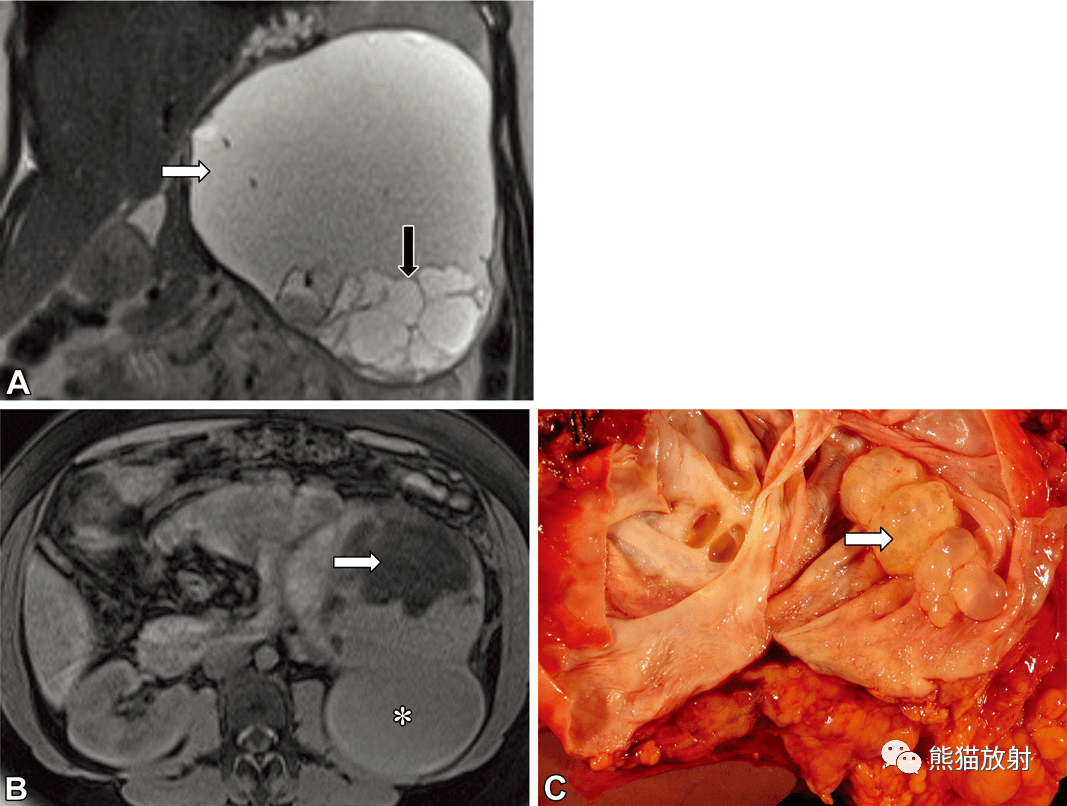

腹盆部产生粘液肿瘤丨疾病种类及mri表现_显示_阑尾_信号

图片尺寸1067x806